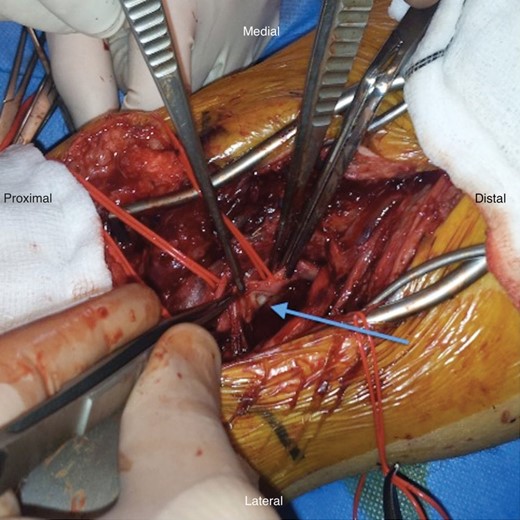

An emergency open repair of the popliteal pseudoaneurysm was undertaken. During the surgery, an S-shaped incision was made in the popliteal fossa. Initial dissection was difficult because of the overlying popliteal vein and tributaries. After achieving proximal and distal control, the pseudoaneurysm was opened and clot was evacuated (Fig. 3). The arterial injury was easily identified at the proximal end of the pseudoaneurysm (Fig. 4) and was closed with a patch of short saphenous vein (Fig. 5).